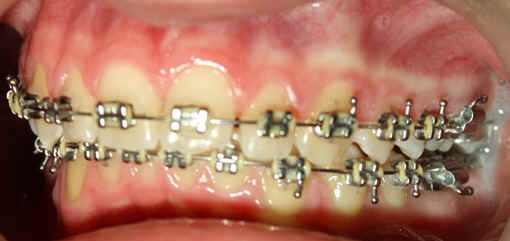

Intra-op 2009/09/10 U wire .018, L .020